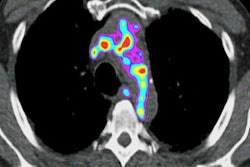

Indeed, clinicians know that calcium caused by plaque is a key indicator of heart disease. However, SPECT, the most widely used modality to image calcium, can expose patients to an excess amount of radiation. That issue is part of the reason why Intermountain installed its PET/CT scanner four years ago.

"With cardiac PET, we are finding that it has so much more accuracy than SPECT, which we were using," Le said. "Cardiac PET provides so much more for so much less radiation exposure, and with CT we can get anatomical imaging on a scanner that also gives us functional imaging."